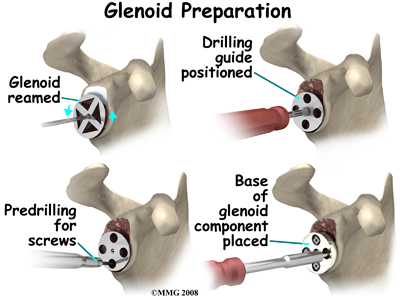

The glenoid will be replaced with a ball of metal. The arthritic glenoid surface is prepared by grinding away any remaining cartilage and flattening the surface. This is done with an instrument called a reamer. The surgeon usually uses the reamer to drill holes into the bone of the scapula and to flatten the deformed glenoid surface so the base plate rests on a smooth, flat surface. This is where the stem of the glenoid component is anchored.